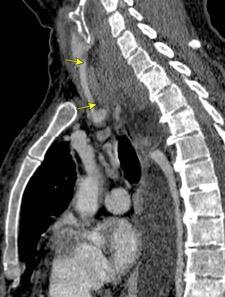

Pliegue axilar Normal

Rehúsa cirugía

2011. Acude por masa axilar

Linfoma NH de cél. B. Invasión Transtorácica.

Afectación axilar